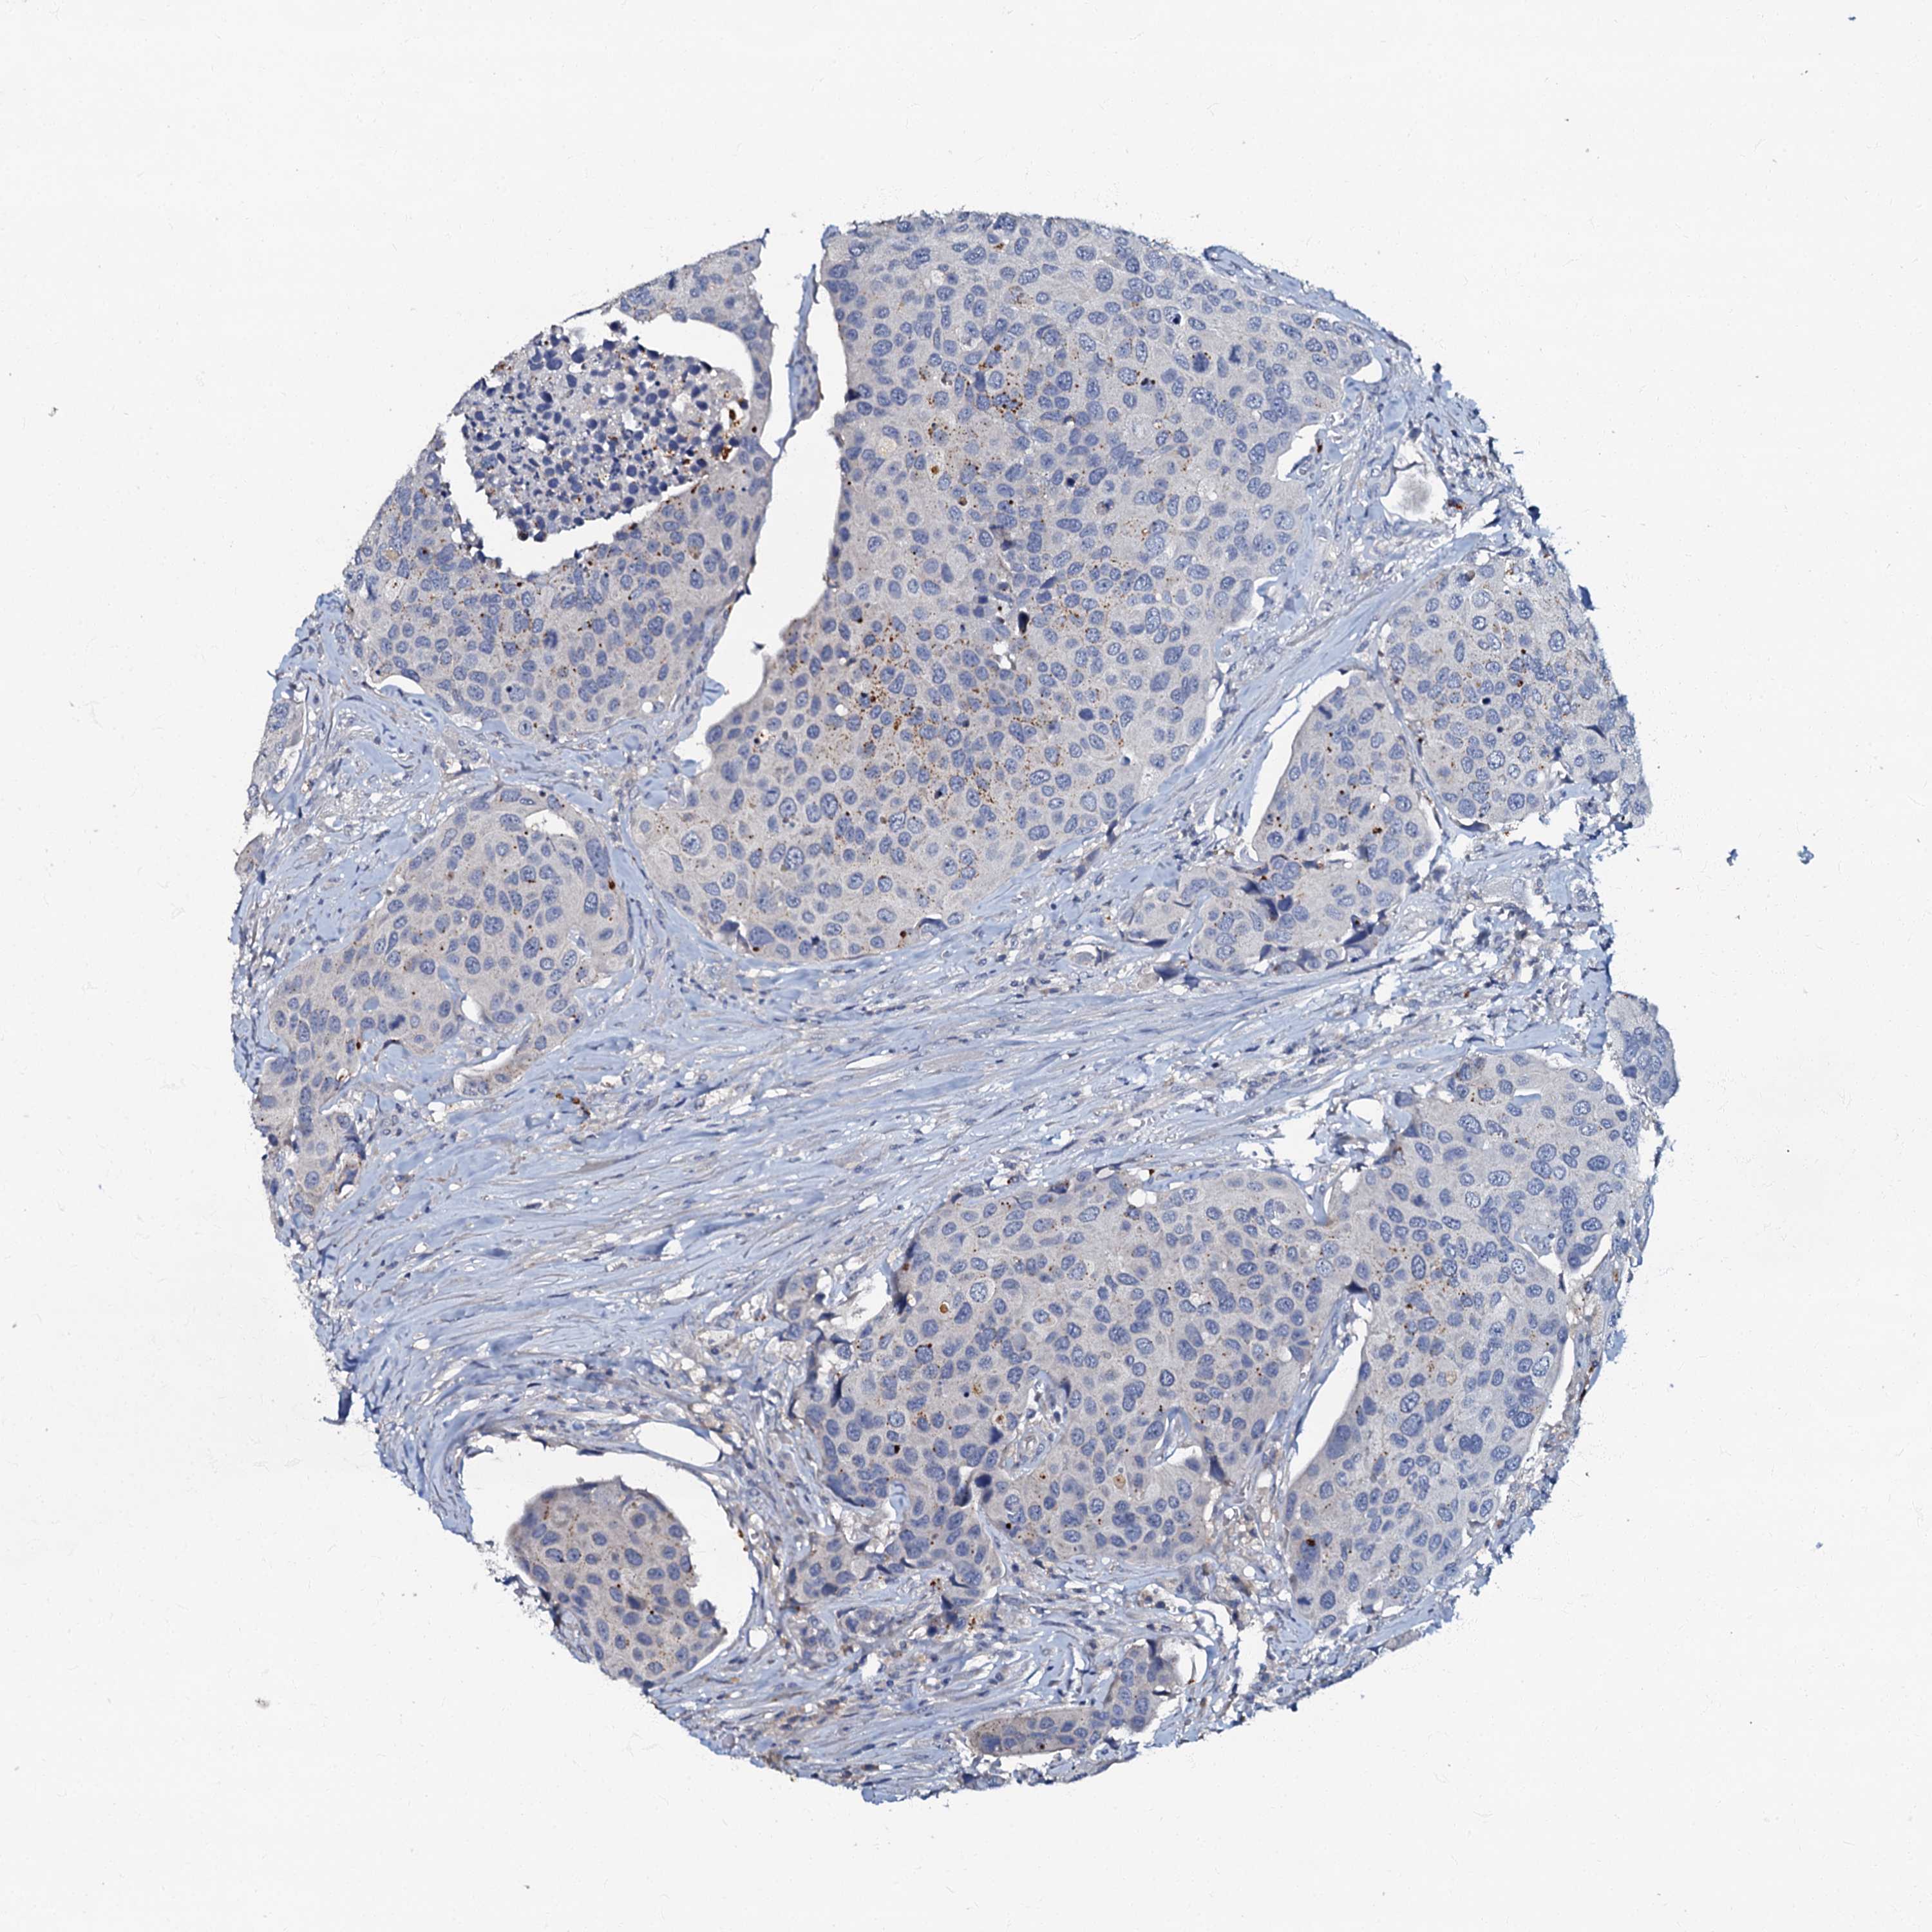

UROTHELIAL CANCER - Protein expressioni

A mouse-over function shows sample information and annotation data. Click on an image to view it in a full screen mode. Samples can be filtered based on level of antibody staining by selecting one or several of the following categories: high, medium, low and not detected. The assay and annotation is described here.

Antibody stainingi

Antibody staining in the annotated cell types in the current human tissue is reported as not detected, low, medium, or high, based on conventional immunohistochemistry profiling in selected tissues. This score is based on the combination of the staining intensity and fraction of stained cells.

Each image is clickable and will lead to virtual microscopy that enables deeper exploration of all samples and also displays staining intensity scores, fraction scores and subcellular localization as well as patient and tissue information for each sample.

Antibody HPA037947

Antibody HPA037948

Urothelial carcinoma, High grade

Urothelial carcinoma, Low grade

Urothelial carcinoma, NOS